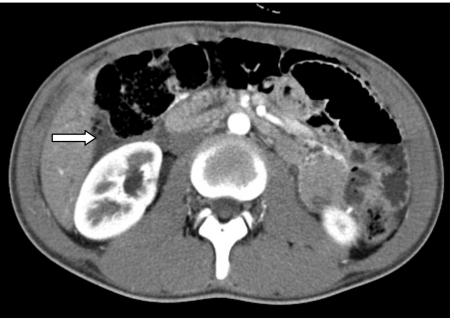

A 15-year-old boy presented with intestinal obstruction two weeks following a blunt abdominal trauma. He had progressive bilious vomiting without abdominal distension or peritonitis. The contrast computed tomography (CT) scan of the abdomen provided the definitive diagnosis: there was an obstructing duodenal hematoma, which might have been slowly progressing or have arisen from secondary hemorrhage after the initial injury. The boy remained stable over a ten-day period of conservative treatment, and his obstructive symptoms and signs were resolved completely. A follow-up CT scan of the abdomen (16 days after admission) showed an almost complete resolution of the hematoma. Delayed duodenal hematoma causing intestinal obstruction has been reported rarely in previous literature. Occasionally a significant secondary hemorrhage resulting in intestinal obstruction can become life threatening. Clinical follow-up is paramount after initial recovery. Although conservative treatment suffices in most cases, the surgeon should be wary of the need for definitive surgical intervention if there is evidence of ongoing acute hemorrhage or of the obstructing hematoma failing to resolve. Laparoscopic drainage of the hematoma provides optimistic results for patients failing conservative management.

一名15岁男孩在腹部钝性创伤两周后出现肠梗阻。他有进行性胆汁性呕吐,无腹胀或腹膜炎。腹部对比计算机断层扫描(CT)明确诊断为:存在梗阻性十二指肠血肿,可能是缓慢进展或由初始损伤后的继发性出血引起。该男孩在为期十天的保守治疗期间病情稳定,梗阻症状和体征完全消失。腹部随访CT扫描(入院16天后)显示血肿几乎完全消退。以往文献中很少报道延迟性十二指肠血肿导致肠梗阻。偶尔,严重的继发性出血导致肠梗阻可能危及生命。初始恢复后临床随访至关重要。虽然大多数情况下保守治疗就足够了,但如果有持续急性出血或梗阻性血肿未消退的证据,外科医生应警惕是否需要进行确定性手术干预。对于保守治疗失败的患者,腹腔镜引流血肿可取得乐观效果。